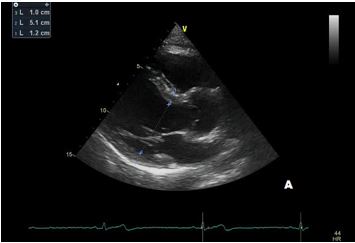

After a year, our patient underwent TTE that showed an aortic root dimension of 44 (Figure C), stable in comparison with the previous evaluation, with no modification of ascending aorta measurement and no LV enlargement (Figure A and B). He continues with yearly follow-up, continuing with personalized physical activity previously prescribed.

Fig A Flavio - Aortic root dilation in competitive athletes.jpg